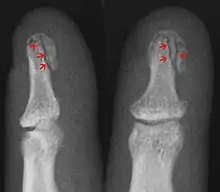

| Photo | Type | Description | Causes | Effects |

|---|---|---|---|---|

| Avulsion fracture | A fragment of bone is separated from the main mass (image shows a Busch fracture) | |||